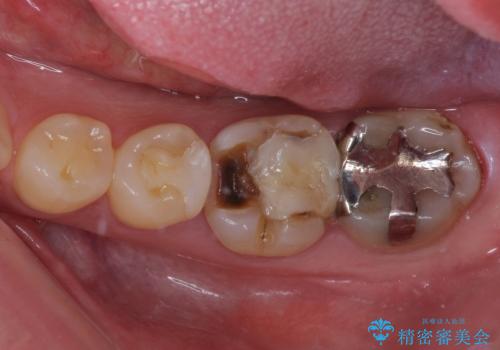

奥歯は虫歯が放置されていましたが、特に症状はなく歯髄の状態も正常でした。

前歯、奥歯ともにオールセラミッククラウンやセラミックインレーにて治療を行うこととしました。